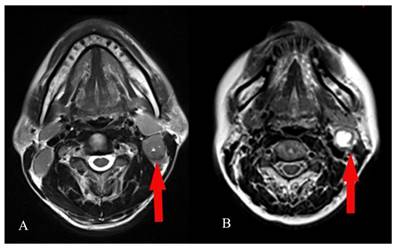

The grading of CNN was evaluated in the largest axial T2-weighted MR plane for an individual necrotic lymph node by visual assessment. The grading criteria for CNN were as suggested by Munck et al: grade 0 CNN, no hypodense zones in axial T2-weighted MR images; grade 1 CNN, ≤ 33% nodal areas showing hypodense zones in axial T2-weighted MR images; and grade 2, >33% nodal areas showing hypodense zones in axial T2-weighted MR images (Figure 1) [18].

Figure 1

Visual assessment of the grading of cervical node necrosis (CNN) on magnetic resonance imaging (MRI). Examples of grade 1 CNN : ≤ 33% nodal areas showing hypodense zones in axial T2-weighted MR images (A) and grade 2 CNN: >33% nodal areas showing hypodense zones in axial T2-weighted MR images (B).